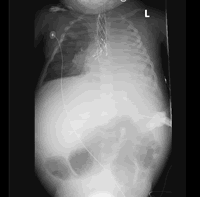

Leah was born with numerous defects, never picked up on any scan during pregnancy. She was born with only a right kidney, her left lung was collapsed, she had a narrowed trachea (Congenital Long Segment Tracheal Stenosis), her left pulmonary artery developed incorrectly and she had a few heart problems (PDA, ASD and Cor-Triatiam). We were told by the dr that they last saw this type of stenosis 15 years ago and that the baby was transferred to London to be operated on. They had no answers or solution. They are not able to do the operations necessary to save Leah's life. Our whole world and all our dreams for our little girl came down in pieces... |

1. Congenital Long Segment Tracheal Stenosis : Narrowed Trachea operated by doing a Slide Tracheoplasty

For the next two months she was taken into theatre 9 times to do a Bronchoscopy and Balloon Dialatation on the trachea and bronchus. Numerous CT-SCANS were also done to see how she was healing on the inside and if the Tracheal Stenosis which was the biggest problem operated on, has healed. Leah has also received blood transfusions a few times.

Due to the poor nutrition Leah's hair is not growing and she is not really picking up weight. They are also giving VitD drops that she needs because she is not in contact with the sun. On the x-rays you can see her teeth and we are sure that they will appear one of these days. |